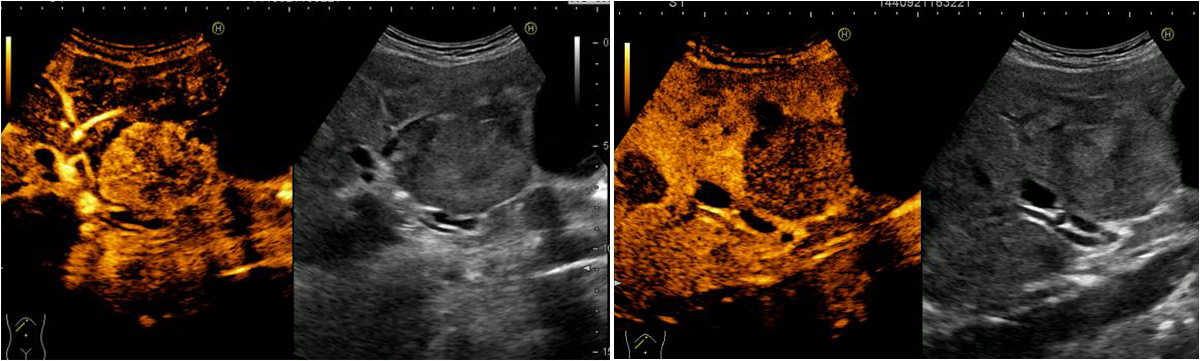

A novel use of Intracavity and intravenous CEUS: The delineation of hepatic abscess formation and conformation of catheter placement. [May 2019]